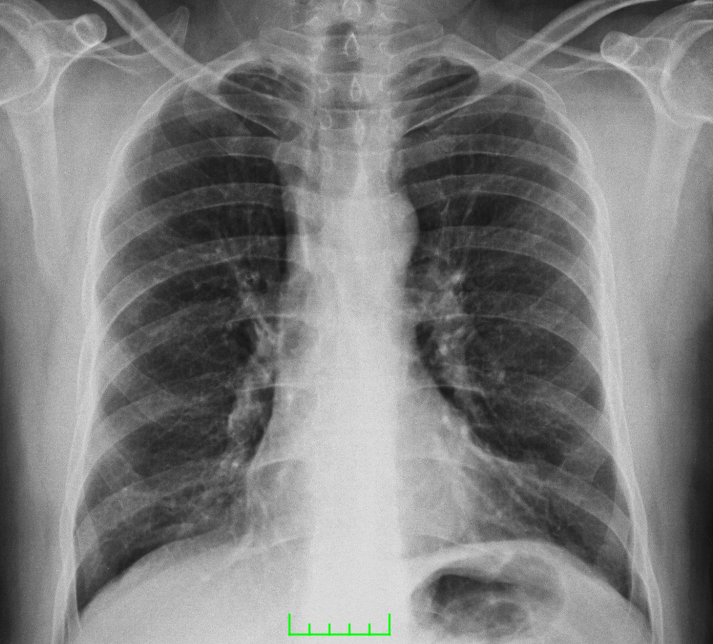

A 40-year-old male patient was admitted to our clinic with complaints of persistent cough for 10 days, phlegm, respiratory distress, fever at intervals, knee pain, and fatigue particularly increased for the past two days. During physical examination, the patient was conscious with poor orientation and cooperation, and was agitated and drowsy. His medical history was able to be obtained from his relatives due to his limited cooperation and orientation. He had a medical history of 20-packyears of smoking and brucellosis 13 years prior. He had a fever of 38.5°C, heart rate was 113 bpm, blood pressure was 100/60 mmHg, and respiration rate was 32/min. Lung auscultation showed bilateral, widespread crepitant rales in all zones of the lungs. Lung sounds were not present in the right basal lung, and dullness was detected with percussion. Cardiovascular examination findings were normal, except for tachycardia. Abdominal examination showed no signs of defense, rebound, or tenderness. Extremities were normal; however, circulatory impairment and cyanosis were present in the periphery. Laboratory test results were as follows: leukocyte 19,900/mm3, hemoglobin 13.7g/dL, hematocrit 40%, platelet count 270,000/mm3, erythrocyte sedimentation rate (ESR) 88mm/hour, and C-reactive protein (CRP) was 15.1 mg/dL. Arterial blood pressure analysis showed that pH was 7.29, PO2 was 76 mmHg, pCO2 was 22mmHg, HCO3 was 11mmol/L, and satO2:94%. Biochemical analysis of blood showed a Na level of 122mmol/L, aspartate aminotransferase (AST) level of 306 IU/mL, and alanine aminotransferase (ALT) of 143.6IU/mL. Metabolic acidosis was present in the arterial blood gas. A posteroanterior radiograph showed bilateral pneumonic infiltration and pleural effusion on the right side (Figure 1). Thoracic computed tomography (CT) showed multiple opacities and right-sided pleural effusion (Figure 2). Serum agglutination titer for Brucella was 1:320. Pleural fluid obtained on thoracentesis was consistent with exudate and hemorrhagic. Pleural fluid tested positive for Rose-Bengal test. Based on clinical and physical examination findings, the patient was diagnosed with brucellosis with lung and pleural involvement. The patient was initiated on ceftriaxone 2 g bid, doxycycline 100 mg bid, and rifampicin 600 mg once daily. His general condition improved on Day 15 of treatment and did not have fever for five days. He was discharged with the recommendation of outpatient follow-up visits. Doxycycline 100 mg bid and rifampicin 600 mg once daily treatment was scheduled to continue until two months (Figures 3 & 4).

Figure 3